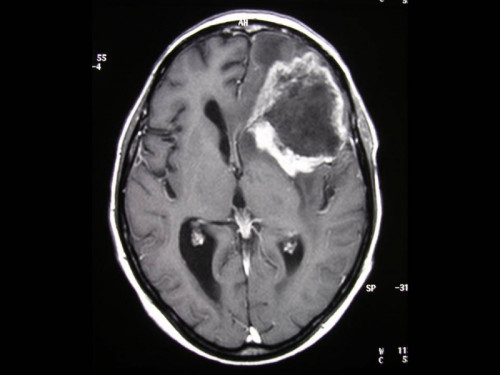

Fall-ID: 172

ICD: C71.9

62-jährige Frau. Ihr Ehemann macht sich langsam Sorgen, weil sie mit ihm recht ungeduldig geworden ist, ja teilweise sogar aggressiv wirkt. Sonst war sie immer von einer so sehr geduldigen und sanften Natur. Selbst gegenüber den Enkelkindern verhält sie sich teilweise merkwürdig. Beim letzten Besuch der drei Enkel hatte sie den Namen des Jüngsten vergessen.